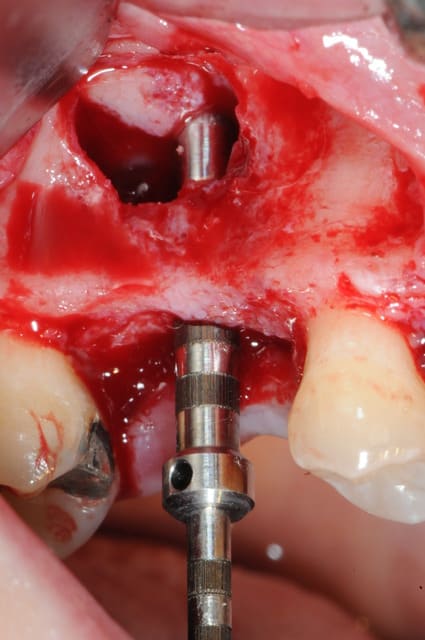

je sais pas si c'est un produit miracle, mais pour les sinus lift, c'est fantastique.

outre le fait de stabiliser un implant dans un sinus type SA4, pas de risque de voir partir le produit comme avec les granules de bioos et autres..

l'autre avantage est de ne pas avoir à mettre de membrane de recouvrement.

je suis donc hyper satisfait du résultat.

jugez plutôt...

l'application type du VitalOs, avec le bone splitting.

le protocole tel qu'il est d'écrit voudrait que l'on applique d'abord une couche de vital os en palatin - laisser durcir - mettre l'implant puis mettre une dernière couche.

ici, j'ai mis l'implant- maintenu la membrane de Schneider en poussant avec l'embout sur celle ci et terminer l'injection du produit. c'est l'un des avantages de ce produit, il est livré avec deux embouts donc les deux solutions sont possibles pour une même seringue.